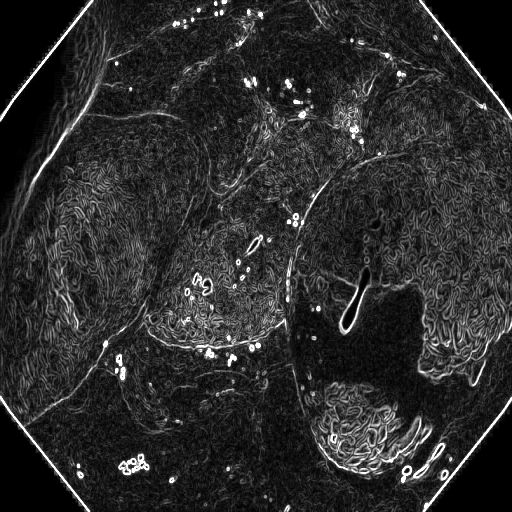

(a) Polyp 1

Refer to caption

(b) Sobel x

(c) Sobel y

(d) Sobel xy

(e) Polyp 2

(f) Sobel x

(g) Sobel y

(h) Sobel xy

Fig. 3: Edge maps of the Sobel operator in x-y directions

The Edge-Guided Feature Enrichment (EGFE) unit actively enhances feature representation by integrating edge knowledge into the set of features. It applies a Sobel operator to the input feature set, generating separate gradient magnitude maps for horizontal (𝒮x)subscript𝒮𝑥(\mathcal{S}_{x})( caligraphic_S start_POSTSUBSCRIPT italic_x end_POSTSUBSCRIPT ) and vertical (𝒮y)subscript𝒮𝑦(\mathcal{S}_{y})( caligraphic_S start_POSTSUBSCRIPT italic_y end_POSTSUBSCRIPT ) directions (Fig. 3). As illustrated in Fig. 3, the Sobel operation in a single direction captures limited information about the polyp. However, combining these maps (Fig. 3(d) and Fig. 3(h)) effectively captures polyp boundaries and enriches learned features. The final gradient magnitude map, produced using the Euclidean norm (Eq. 1), highlights regions with significant intensity changes at polyp boundaries.